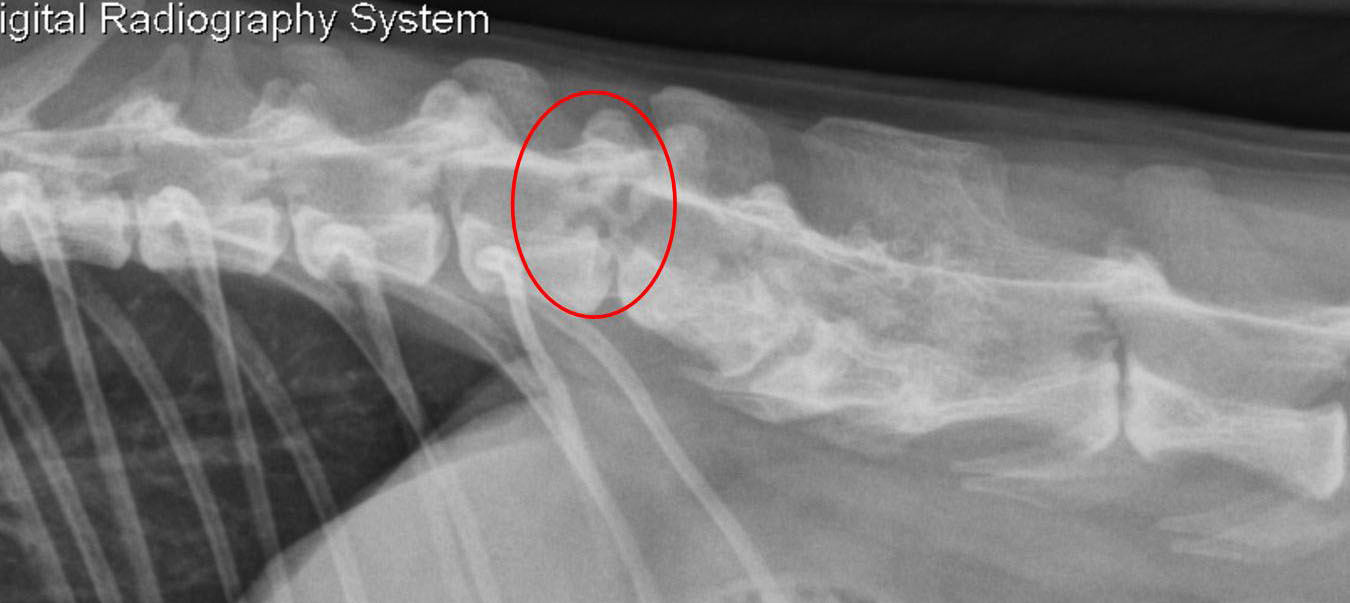

Le spectre vertébral – zoom